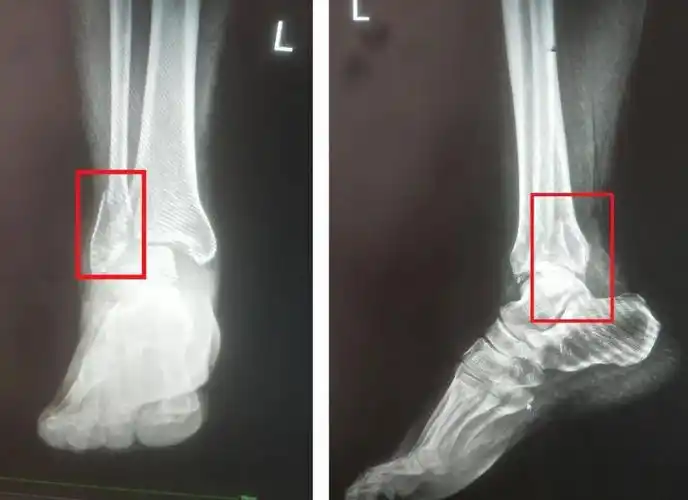

ct显示近日,76岁的李大爷走路不慎摔倒,摔倒时左踝部着地导致左踝部